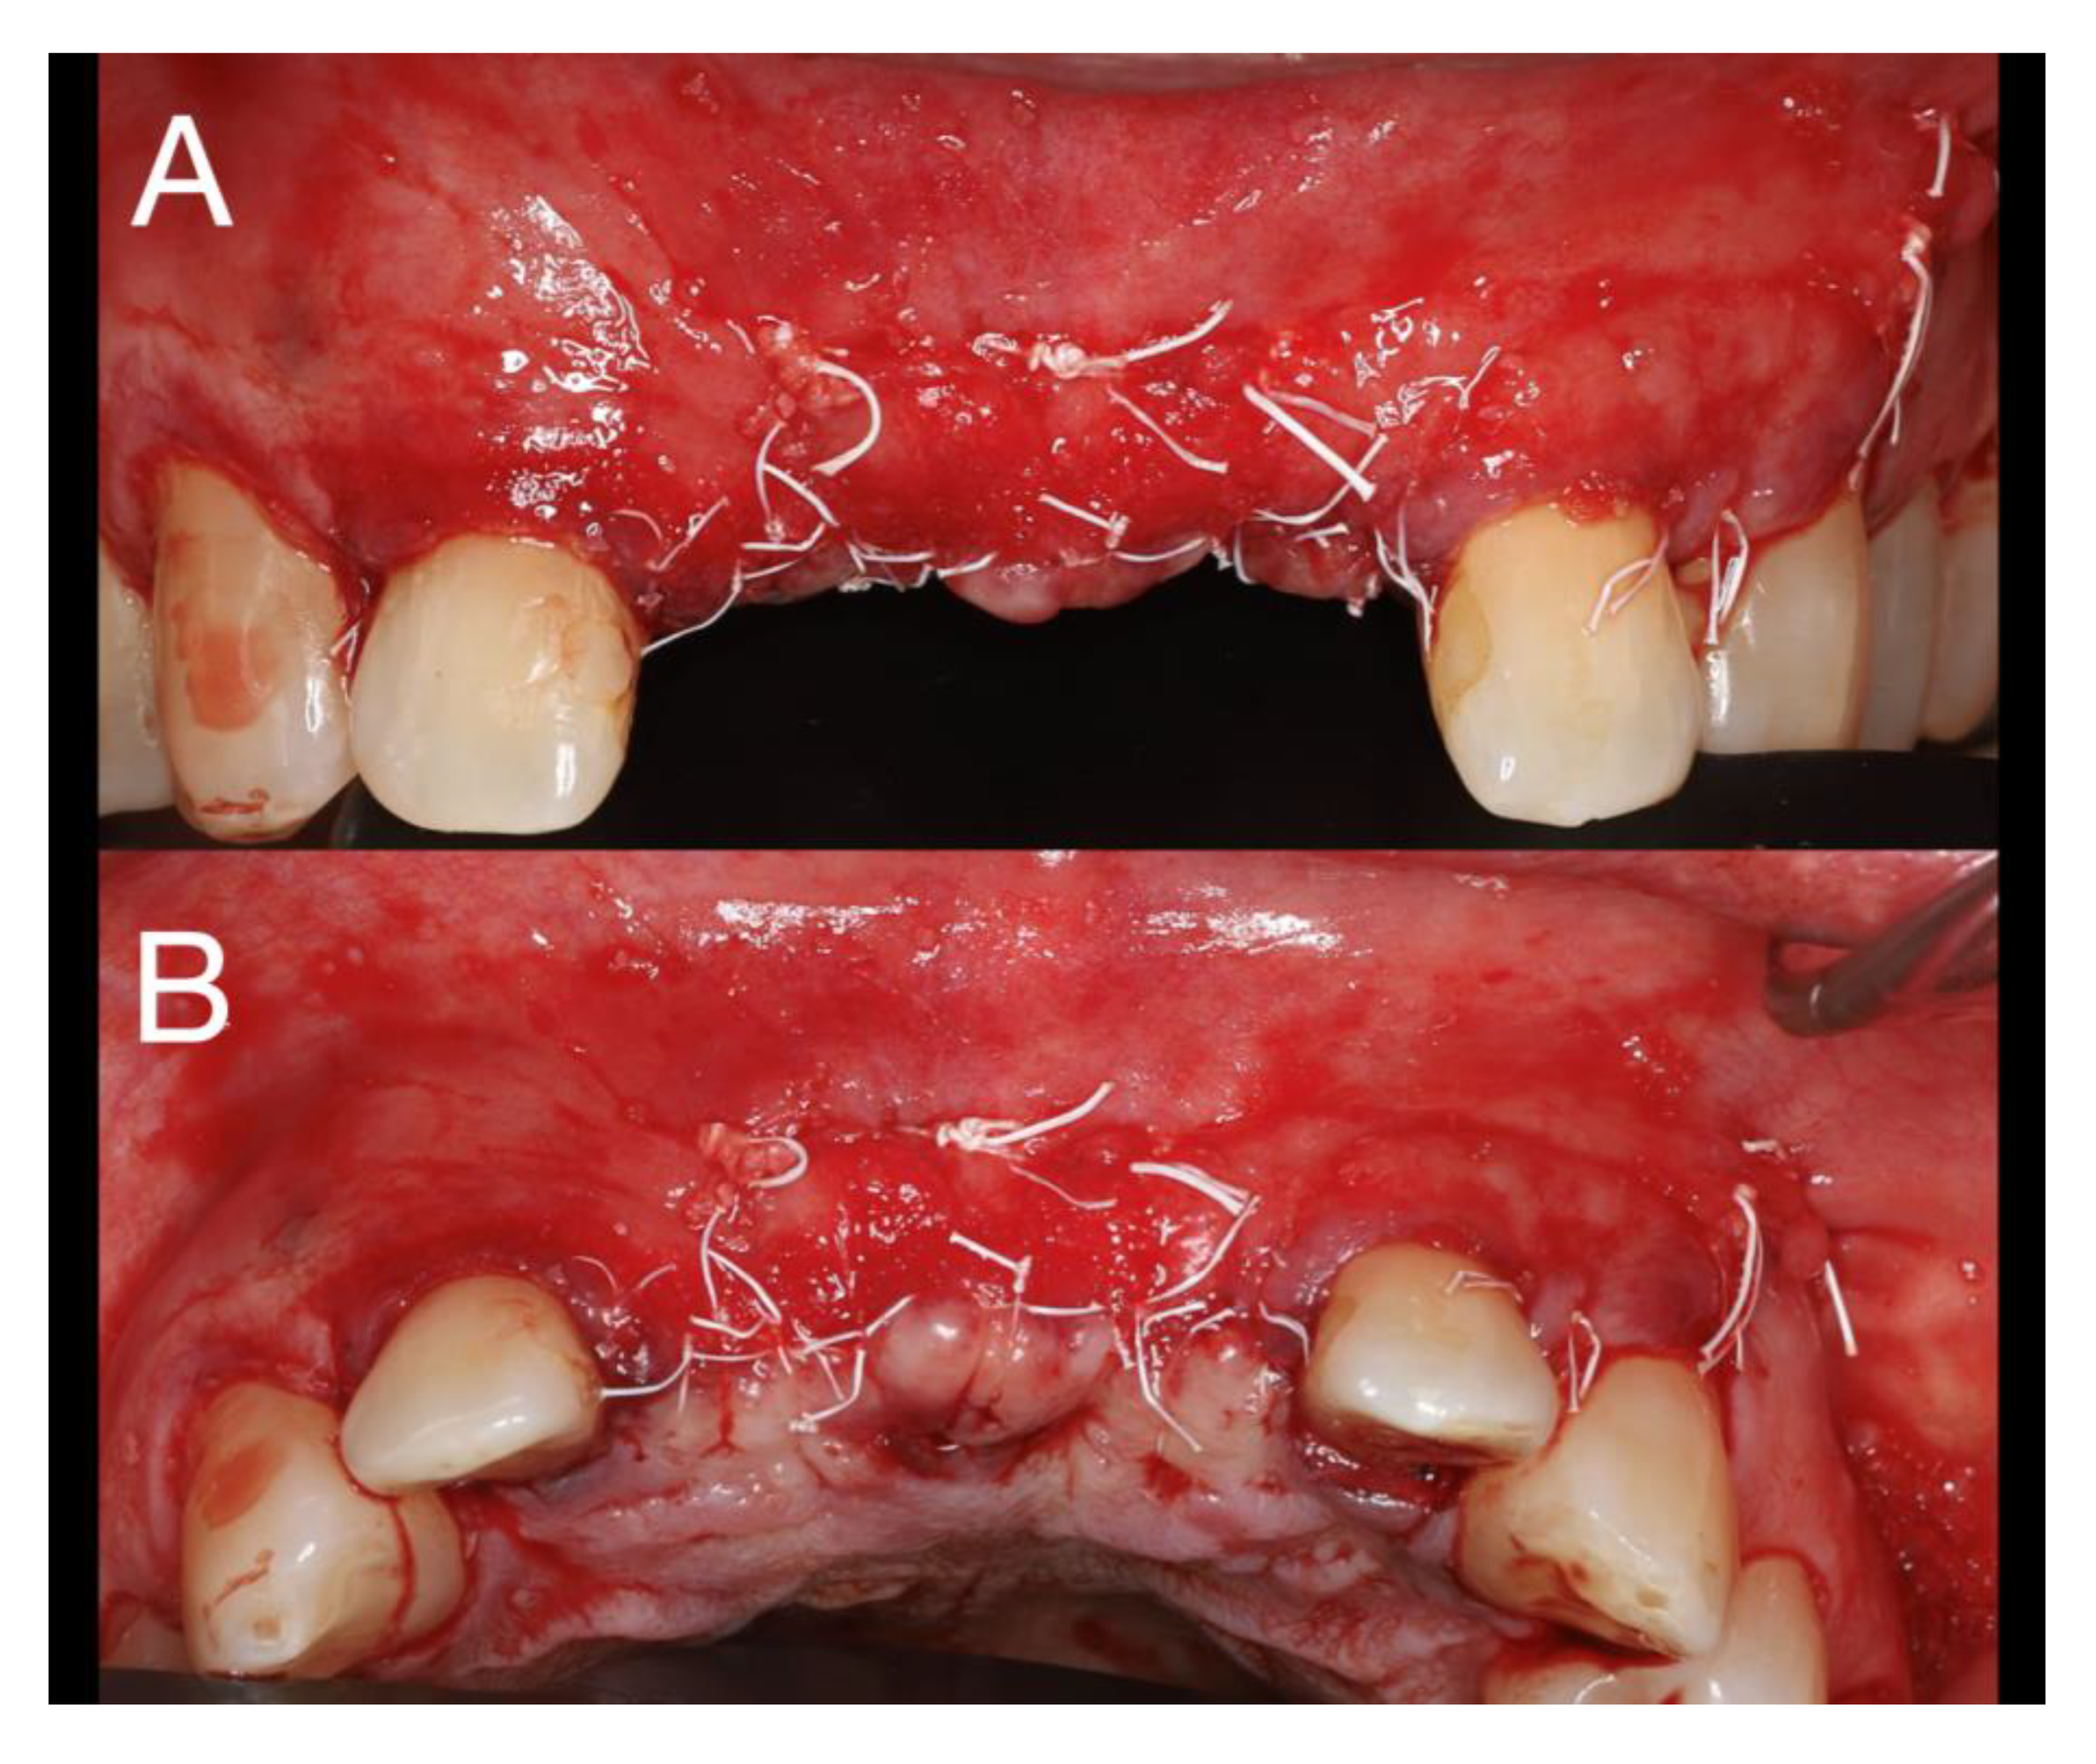

Local anesthesia with articaine (artinibsa® 40mg/ml + 0.01mg/ml, Inibsa®, Spain) was given. A linear incision with a 15 blade was performed form the distal aspect of tooth 13 to mesial of tooth 23 where a releasing incision that cross the mucogingival line was performed. A full thickness flap was elevated, and the cyst was enucleated (Figure 4). During odontogenic of the cyst enucleation (histological established), special attention was given to maintain the integrity of the anterior nasal spine. Even with the carfule enucleation, a communication with the nasal floor occurred and a loss of the palatine bone plate was observed (Figure 4).

Figure 4. Different view after cyst enucleation.

Preprints 77316 g004